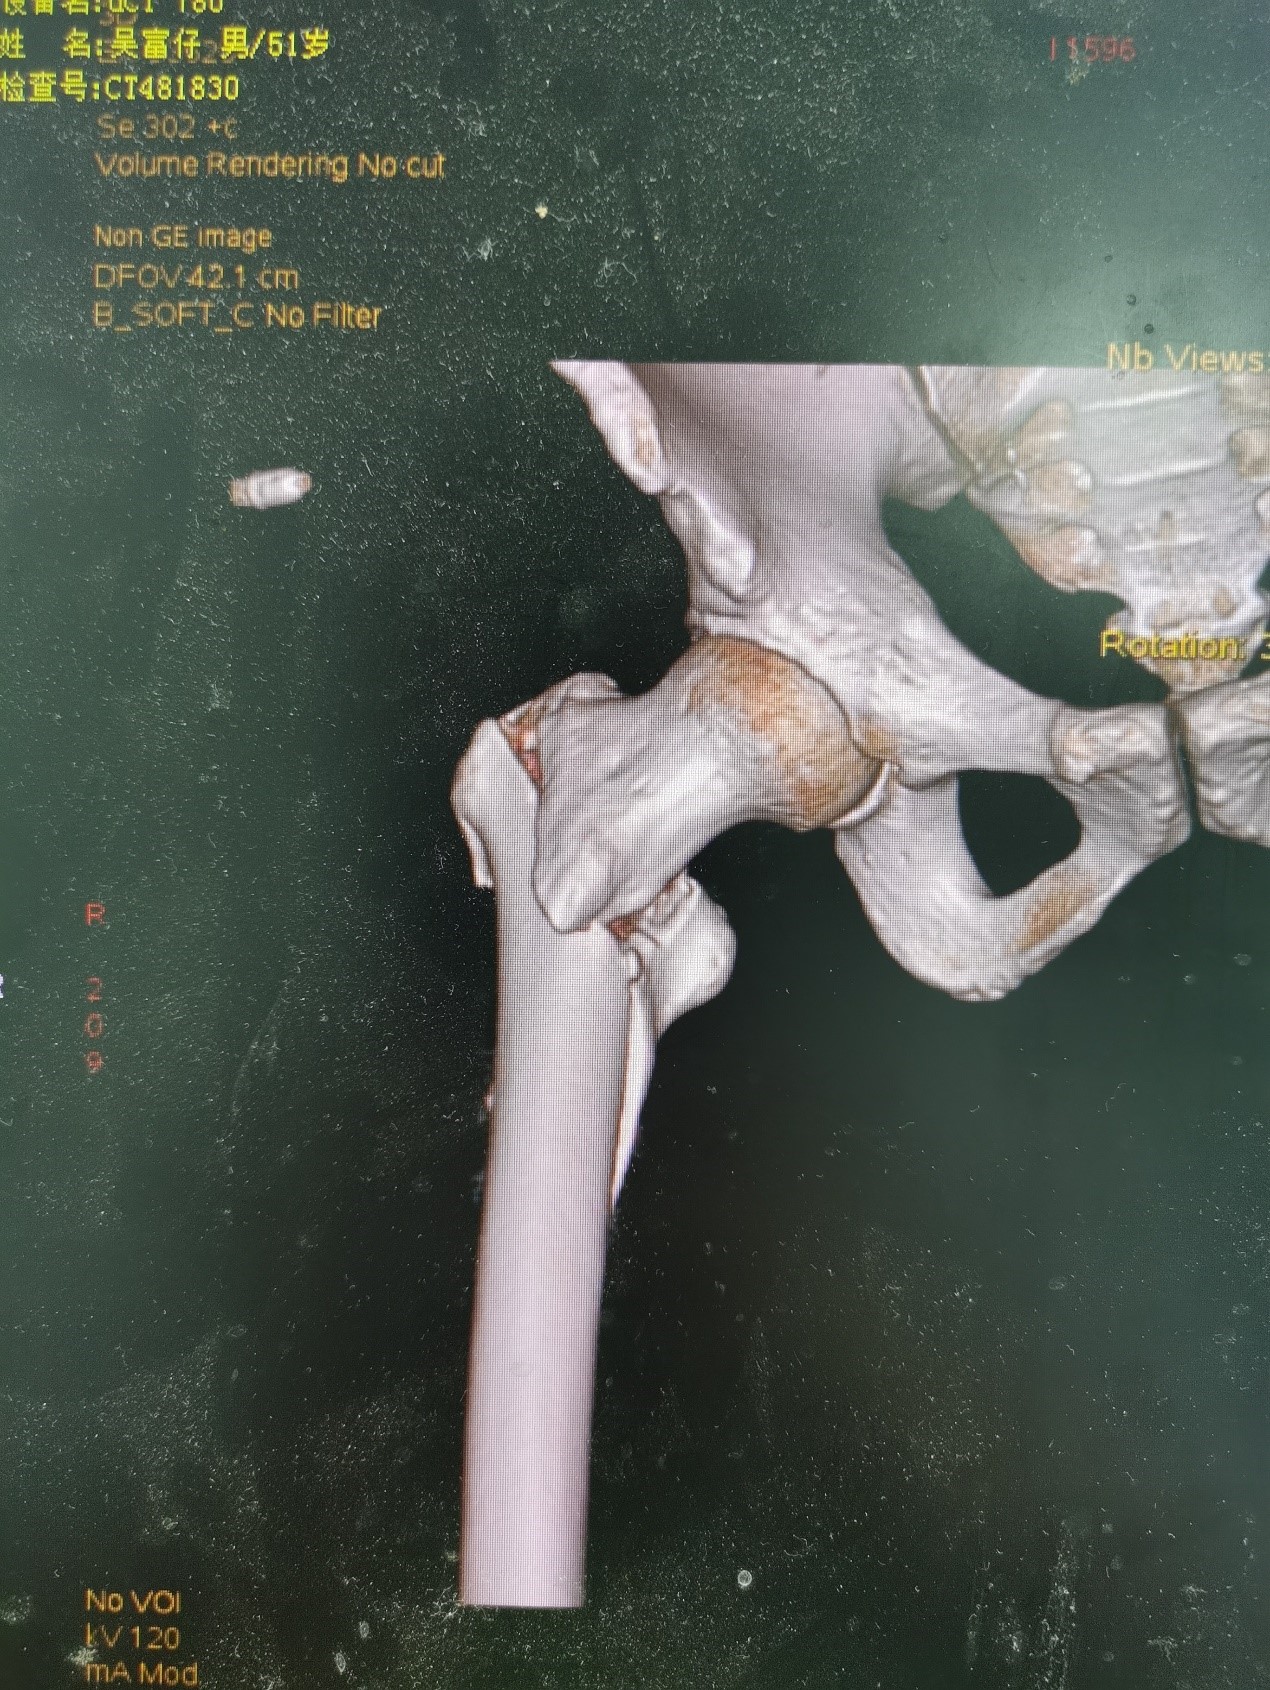

案例二:51岁男性意外摔伤

患者情况:吴先生因路面湿滑不慎摔倒,导致右髋部疼痛并活动受限,经检查确诊为股骨粗隆间骨折。

治疗难点:

1.骨折部位解剖重建的准确性;

2.内固定材料的选择及固定强度的保障。